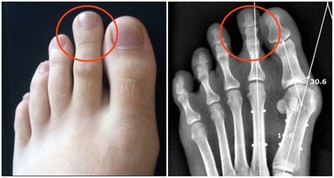

例如,手臂血管內的血栓發展到後期,會使皮膚表面出現大面積潰瘍;

有些患者的手臂上會留有大塊黑斑,或是開始褪皮。

當皮膚組織因為血栓而開始病變時,說明身體內部已經受到了嚴重損傷。